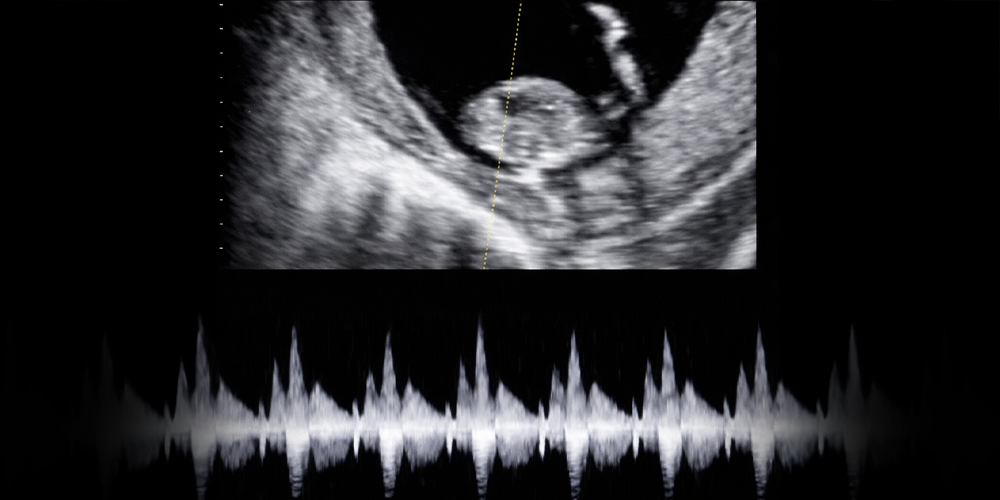

İlk Kalp Atışı

Bu dönemde kalp atışları ultrasonda görülebilir ve duyulabilir.

Kalp atışları aşamasına kadar gelen gebeliklerin düşük olma ihtimalleri % 10-15 kadardır. Başka bir söyleyişle sağlıklı devam etme ihtimalleri % 85- 90 kadardır.